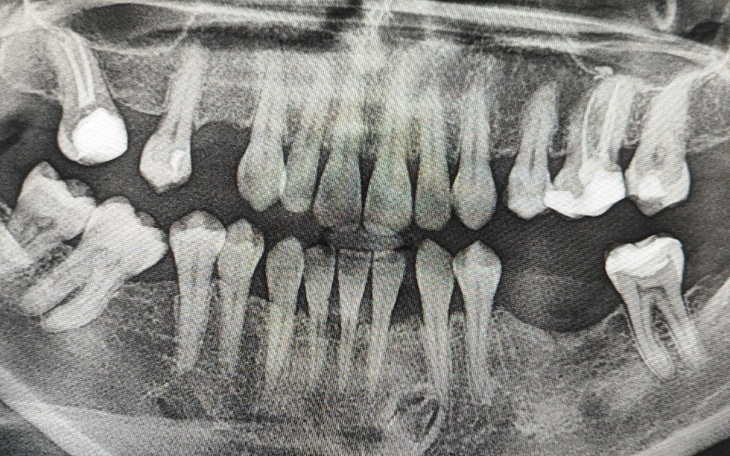

Moje problemy z zdrowiem trwają wiele lat: kłopoty z biodrem - zwapnienie obrąbka, przepuklina w każdym kręgu kręgosłupa sprawiły że skupiłam się na wielu istotnych rzeczach, które pochłonęły moje zasoby finansowe. W między czasie doszły problemy z zębami ,stany zapalne w dziąsłach zmusiły mnie do zrobienia pantomogramu. Okazało się że z lat dzieciństwa mam zatrzymany ząb w dziąśle na skutek czego nigdy mi nie wyrósł i przez to mam przerwę która powoduje rotację zębów to wada zgryzu polegająca na nieprawidłowym ustawieniu zębów innymi słowy zęby obracają się częściowo wokół własnej osi, odbiegając tym samym od oczekiwanego, równego położenia , w tej sytuacji ortodonta zamierza wprowadzić leczenie aparatem niestety dla mnie to koszt jest bardzo wysoki ; 1 łuk kosztuje 2700x 2 plusk koszty wycisku i badanie cefalometrii przewyższają moje zasoby finansowe .